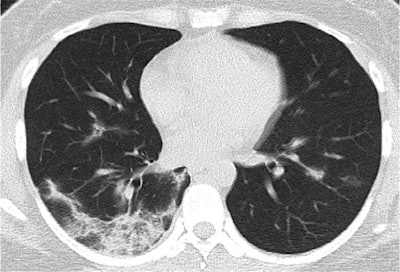

- Days 0 to 5: CT abnormalities progressed rapidly upon symptom onset. The predominant CT finding was ground-glass opacity in 62% of patients, followed by consolidation. Together, these two abnormalities constituted about 85% of all findings during this period. The distribution of lung abnormalities was bilateral in 85% of patients and often subpleural.

- Days 6 to 11: The CT abnormalities and involvement scores peaked for most patients on day 10. Ground-glass opacity remained the most prevalent finding at 59%, with a marked increase in the proportion of the pure ground-glass opacity subtype.

- Days 12 to 17: The severity of the abnormalities mostly persisted throughout this period, without any substantial change in CT scores or number of lung zones involved. Starting from day 12, mixed pattern became the second most prominent finding -- appearing in 38% of patients -- with ground-glass opacity falling to 45%.

- Days 18 to 24: Approximately 94% of the patients' final CT scans continued to show evidence of mild to substantial lung abnormalities. A reticular pattern also appeared in about 3% of the patients.

The radiologists also used a CT scoring technique to calculate the median number of lung zones affected (five out of a total of six, or three per lung) and lung involvement, which hovered around 25%.

Overall, the CT abnormalities and lung involvement progressed rapidly after symptom onset and peaked roughly six to 11 days later, followed by a persistence in high levels of lung abnormalities. The sensitivity of CT for COVID-19 was 84% during the first five days of illness and 99% from days six to 11.